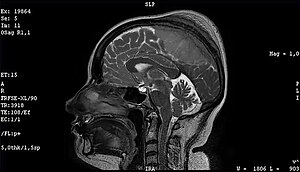

Файл:Meningioma of the sagittal sinus isolated.jpg

Доброкачественная опухоль — менингиома средней трети сагиттального синуса и фалькса с большим гиперостозом